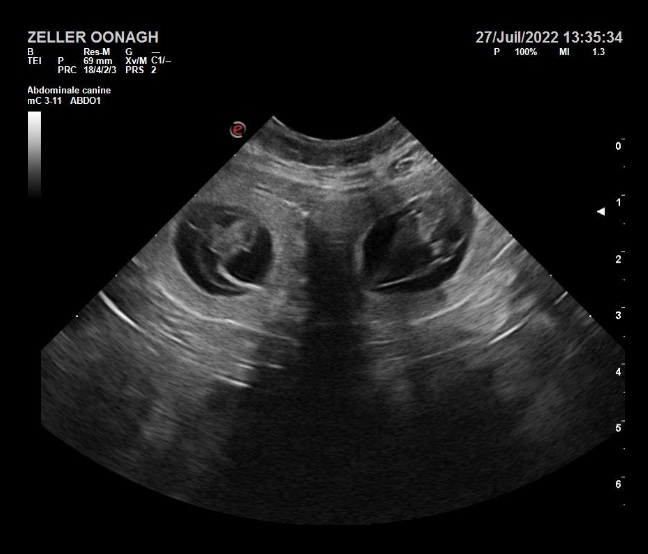

L’échographie

Dans le meilleur des cas où il y’aura eu saillie. Il sera nécessaire d’effectuer à 28 jours de potentielle gestation un contrôle chez le vétérinaire, afin de vérifier si la saillie a fonctionné et de compter le nombre de fœtus à venir. Il est essentiel de connaitre approximativement le nombre de chiots attendus pour préparer au mieux la mise bas et commencer à prendre les réservations des futurs adoptants. Il est possible qu’une saillie ait eu lieu, mais que votre chienne pour plusieurs raisons reste vide, cela arrive régulièrement, c’est aussi une option à envisager. Dans ce cas-là, la déception est grande. Tout ce temps, cette énergie dépensée, tous ces projets et ces plannings mis en place qu’il faudra recommencer. Sans parler des futurs adoptants, avec qui vous aurez passé du temps pour définir s’ils seront de bons maîtres et à qui il faudra annoncer la mauvaise nouvelle…